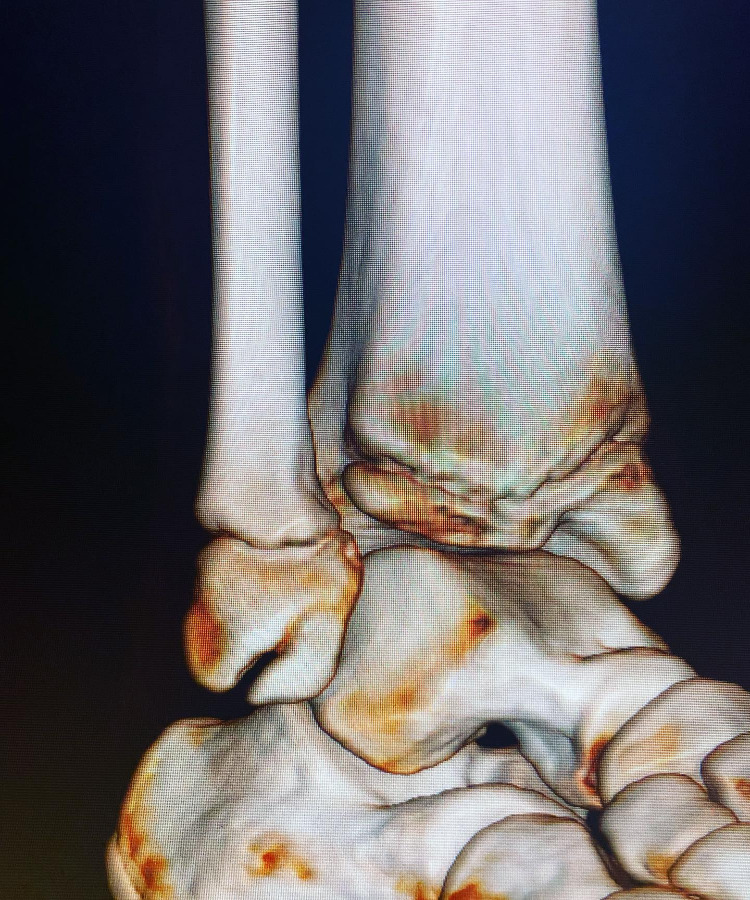

El pie equinovaro es una deformidad congénita donde el pie está en punta y la planta girada hacia adentro.

conocer másEl pie equinovaro es una deformidad congénita donde el pie está en punta y la planta girada hacia adentro.